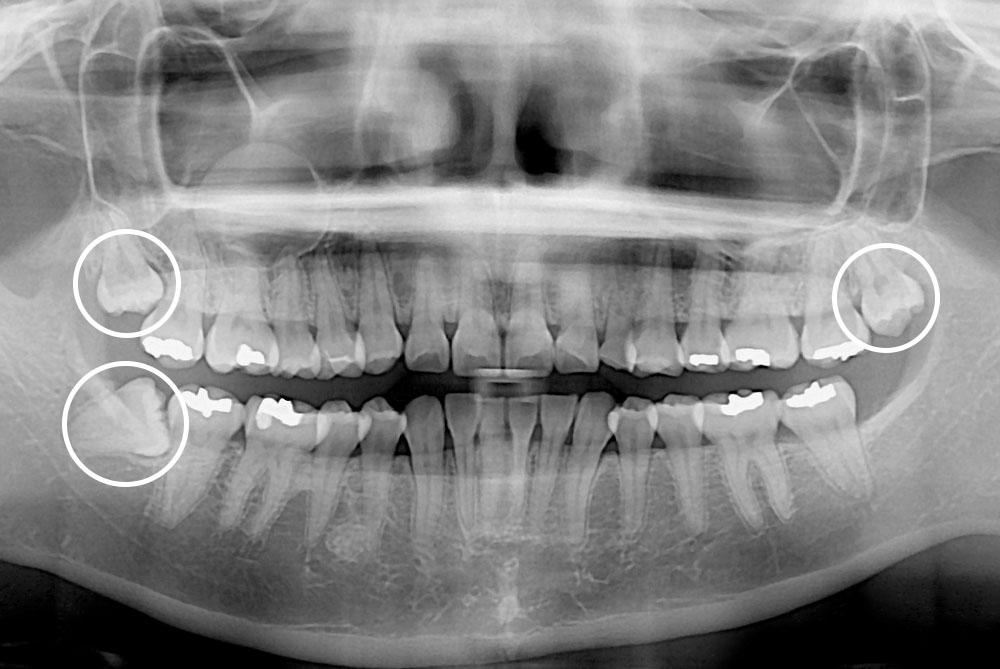

[사랑니] 매복 사랑니 발치

치료후 : 2020-07-25

세종치과는 구강악안면외과학 박사이신 원장님이 발치하는 치과입니다.